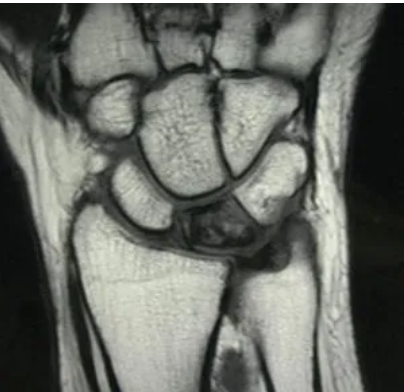

Qual o padrão da doença de Kienbock na RNM ?

A

T1 (hipossinal)

T2 (hiperssinal)